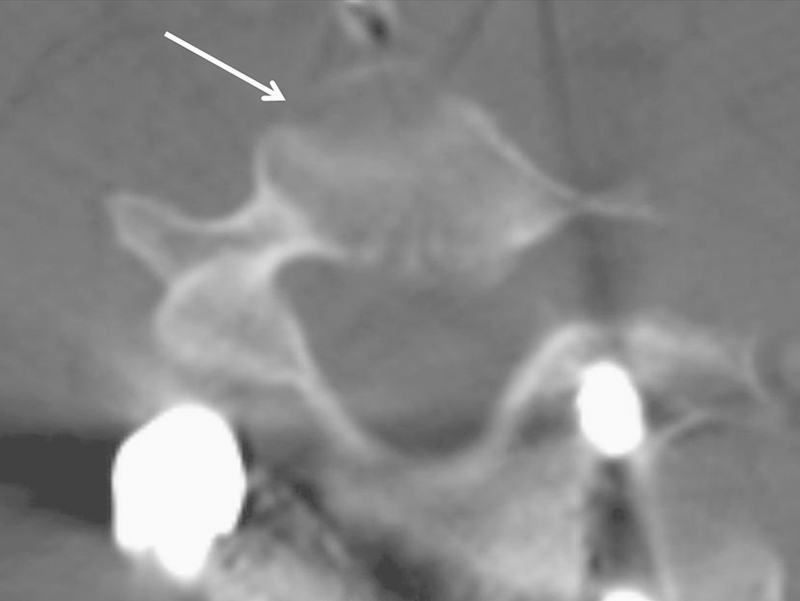

研究设计案例报告。临床目的是报道导丝辅助椎弓根螺钉置入与喉返神经(RLN)神经失用症之间先前未知的关联,以及这种关联如何与Tapia综合征的症状重叠;我们还报告了我们对该患者的临床管理方法。方法1例17岁男性特发性脊柱侧凸患者经后路内固定及T1-L1关节融合术后出现Tapia综合征。拔管后,患者声音沙哑,吞咽困难。影像学显示T1前体皮层与右侧RLN相对应的裂口。结果耳鼻喉科检查发现右声带不动,喉内感觉减弱,软喉镜下分泌物淤积提示右侧颅神经X损伤,左侧舌偏。在病人被送回家之前,在改良的钡吞咽过程中误吸促使插入经皮内窥镜胃造口管。术后第20天,钡剂吞咽显示误吸减少,患者报告症状完全缓解。取下饲管,1个月后恢复正常饮食。Tapia综合征,或持续性单侧喉部和舌下麻痹,是一种罕见的神经失用症,以前未观察到其与T1沿RLN路径的椎体破裂有关。结论Tapia综合征在术后症状持续时应作为鉴别诊断的考虑因素,脊柱外科医生应意识到这是脊柱内固定导丝的潜在并发症。

Study Design Case report. Clinical Question The clinical aim is to report on a previously unknown association between guidewire-assisted pedicle screw insertion and neuropraxia of the recurrent laryngeal nerve (RLN), and how this may overlap with the signs of Tapia syndrome; we also report our approach to the clinical management of this patient. Methods A 17-year-old male patient with idiopathic scoliosis experienced Tapia syndrome after posterior instrumentation and arthrodesis at the level of T1-L1. After extubation, the patient had a hoarse voice and difficulty in swallowing. Imaging showed a breach in the cortex of the anterior body of T1 corresponding to the RLN on the right. Results Otolaryngological examination noted right vocal fold immobility, decreased sensation of the endolarynx, and pooling of secretions on flexible laryngoscopy that indicated right-sided cranial nerve X injury and left-sided tongue deviation. Aspiration during a modified barium swallow prompted insertion of a percutaneous endoscopic gastrostomy tube before the patient was sent home. On postoperative day 20, a barium swallow demonstrated reduced aspiration, and the patient reported complete resolution of symptoms. The feeding tube was removed, and the patient resumed a normal diet 1 month later. Tapia syndrome, or persistent unilateral laryngeal and hypoglossal paralysis, is an uncommon neuropraxia, which has previously not been observed in association with a breached vertebral body at T1 along the course of the RLN. Conclusion Tapia syndrome should be a differential diagnostic consideration whenever these symptoms persist postoperatively and spine surgeons should be aware of this as a potential complication of guidewires in spinal instrumentation.